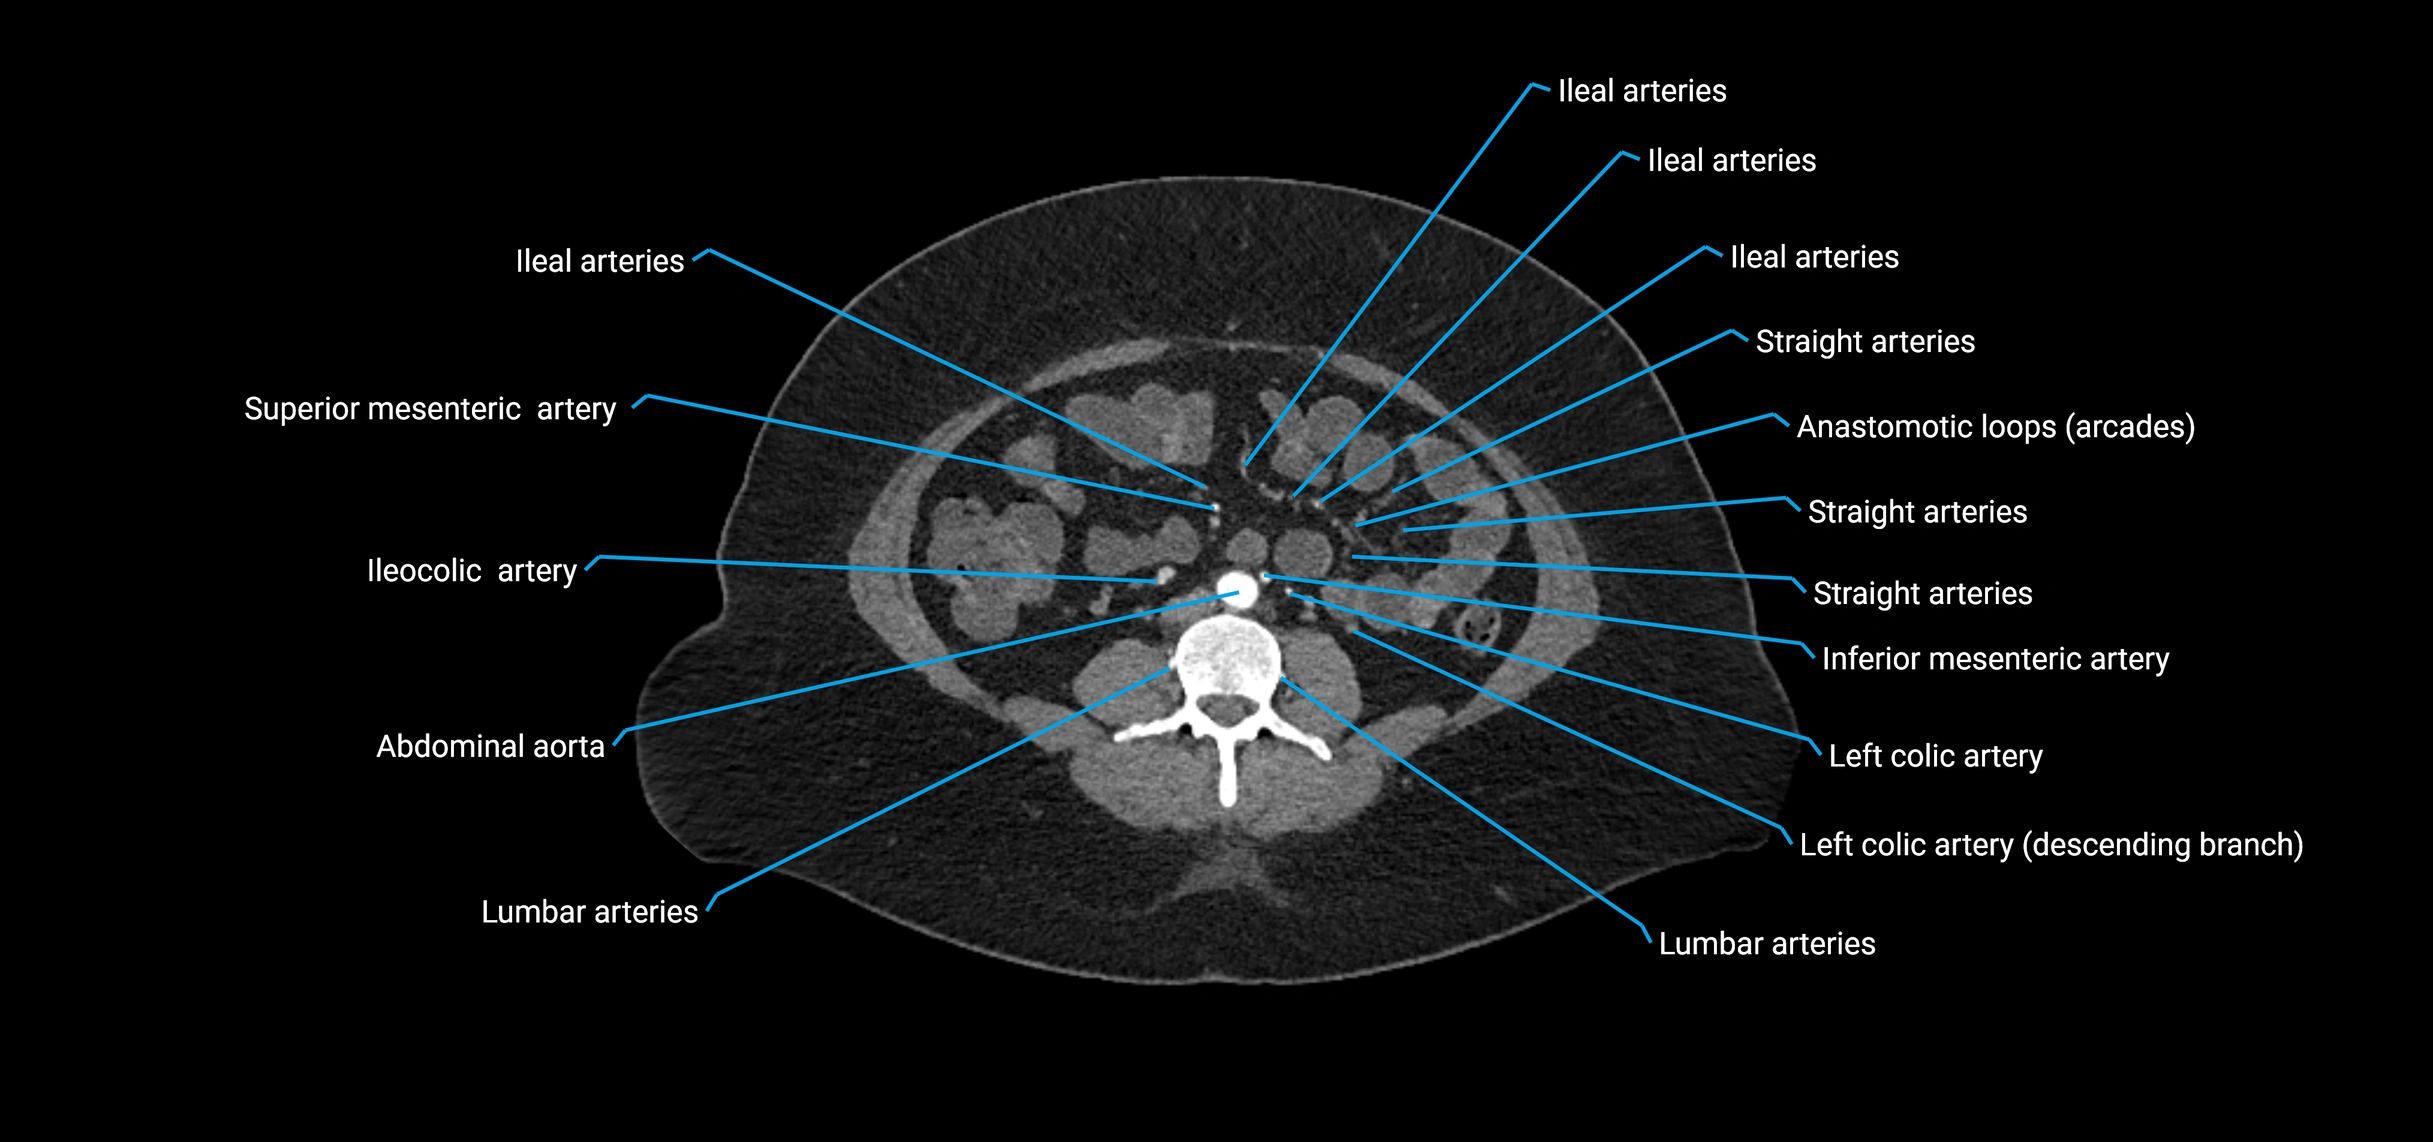

Contrast-enhanced CT (CTA):

• Gold standard for abdominal aortic imaging

• Provides excellent detail of lumen, wall, aneurysm, thrombus, and branch vessels

• Multiplanar and 3D reconstructions help in aneurysm measurement, stent graft planning, and dissection evaluation